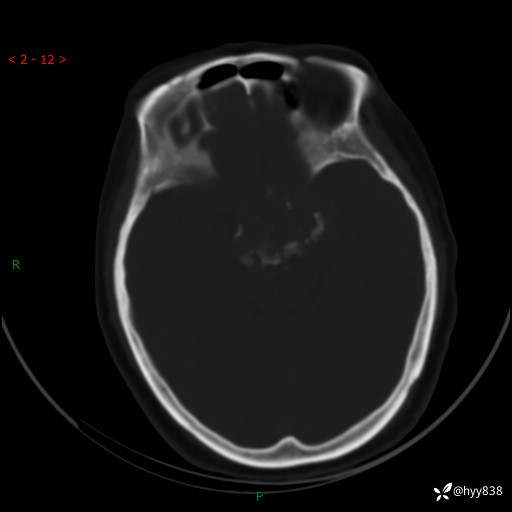

老年女性,视力下降3年。鞍区钙化性肿块,鉴别诊断有哪些---(有结果)

简要病史:患者3年前无明显诱因左眼出现视力下降,出现视物模糊,无头痛,无头晕,无恶心、呕吐,无意识障碍,无肢体麻木及抽搐,无心慌、胸闷,无腹痛、腹胀等不适,无旋地转感。个月前右眼视力下降,患者视物模糊逐渐下降,自诉看东西有雾感。在当地医院眼科就诊,症状无好转,行头部MR提示:鞍区肿物。现患者为求诊治来我科就诊,在当地市中医医院行头部CT:提示鞍区占位。患者现求进一步诊治来我院就诊,门诊以“鞍区肿物”收入我科。 患病以来,患者精神、饮食、睡眠尚欠佳,大小便如常,体力体重无明显变化。

临床诊断:鞍区肿物

颅脑CT平扫